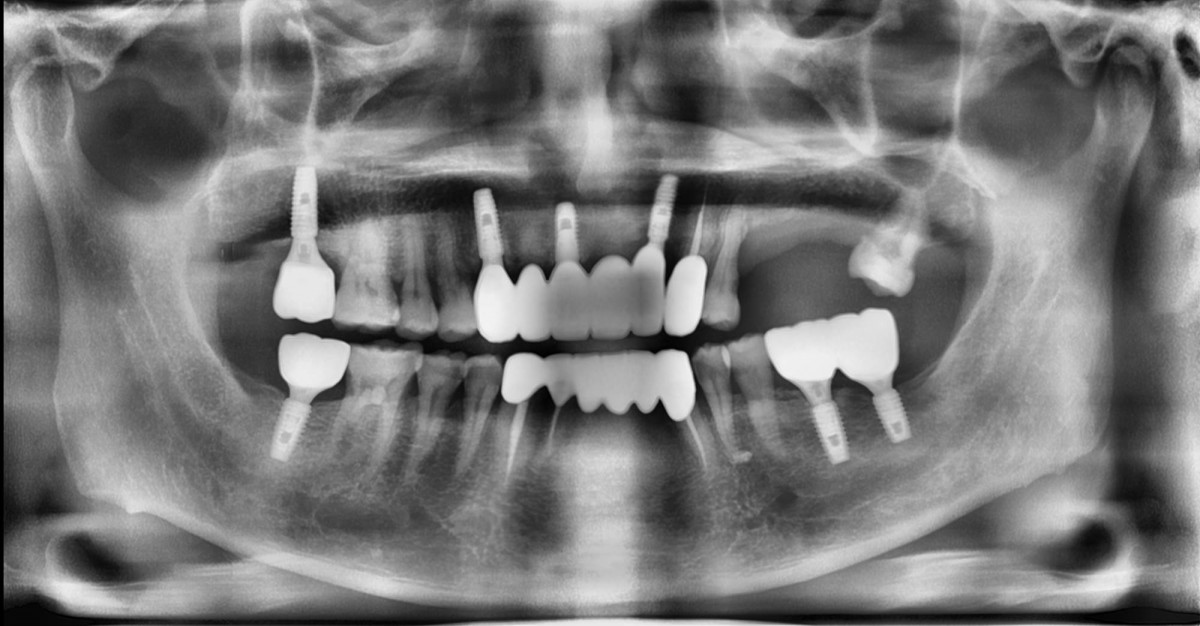

<GCpbc> A 58-year-old male is a patient undergoing implant installation in various parts. The old Br of the anterior maxilla has fallen

off and it is no longer possible to maintain it even temporarily, so a

treatment plan for the anterior teeth was made.